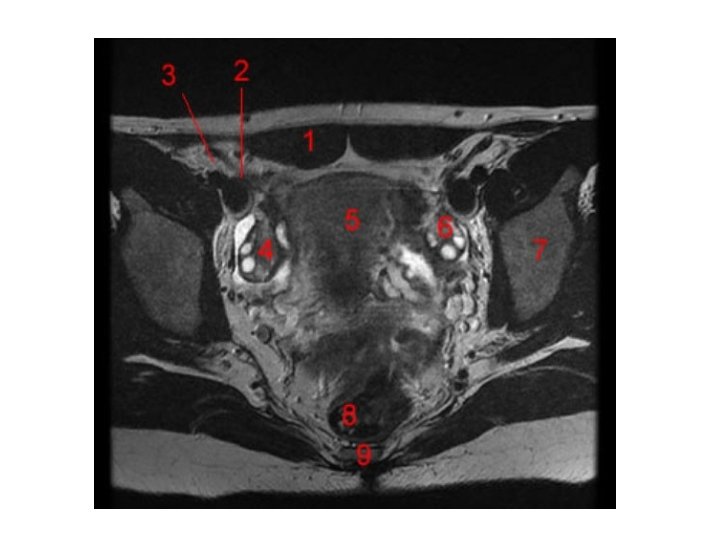

Frontaler Schnitt des weiblichen Beckens Anteile des weiblichen subperitonealen Raumes: -Paracysticum (um die Harnblase) -Paramerium (zwischen den Blättern des Lig. Latum uteri) -Paracolpium (um die Scheide) -Paraproctium( um das Rektum)

Vagina Excavatio vesicouterina Peritoneum Excavatio rectouterina Uterus Portio vaginalis cervicis Vesica urinaria Portio supravaginalis cervicis Fornix vaginae, Pars posterior Fornix vaginae, Pars anterior Vagina, Paries anterior Rectum Urethra Septum rectovaginale Septum vesicovaginale Vagina, Paries posterior Ostium vaginae Vestibulum vaginae Diaphragma urogenitale